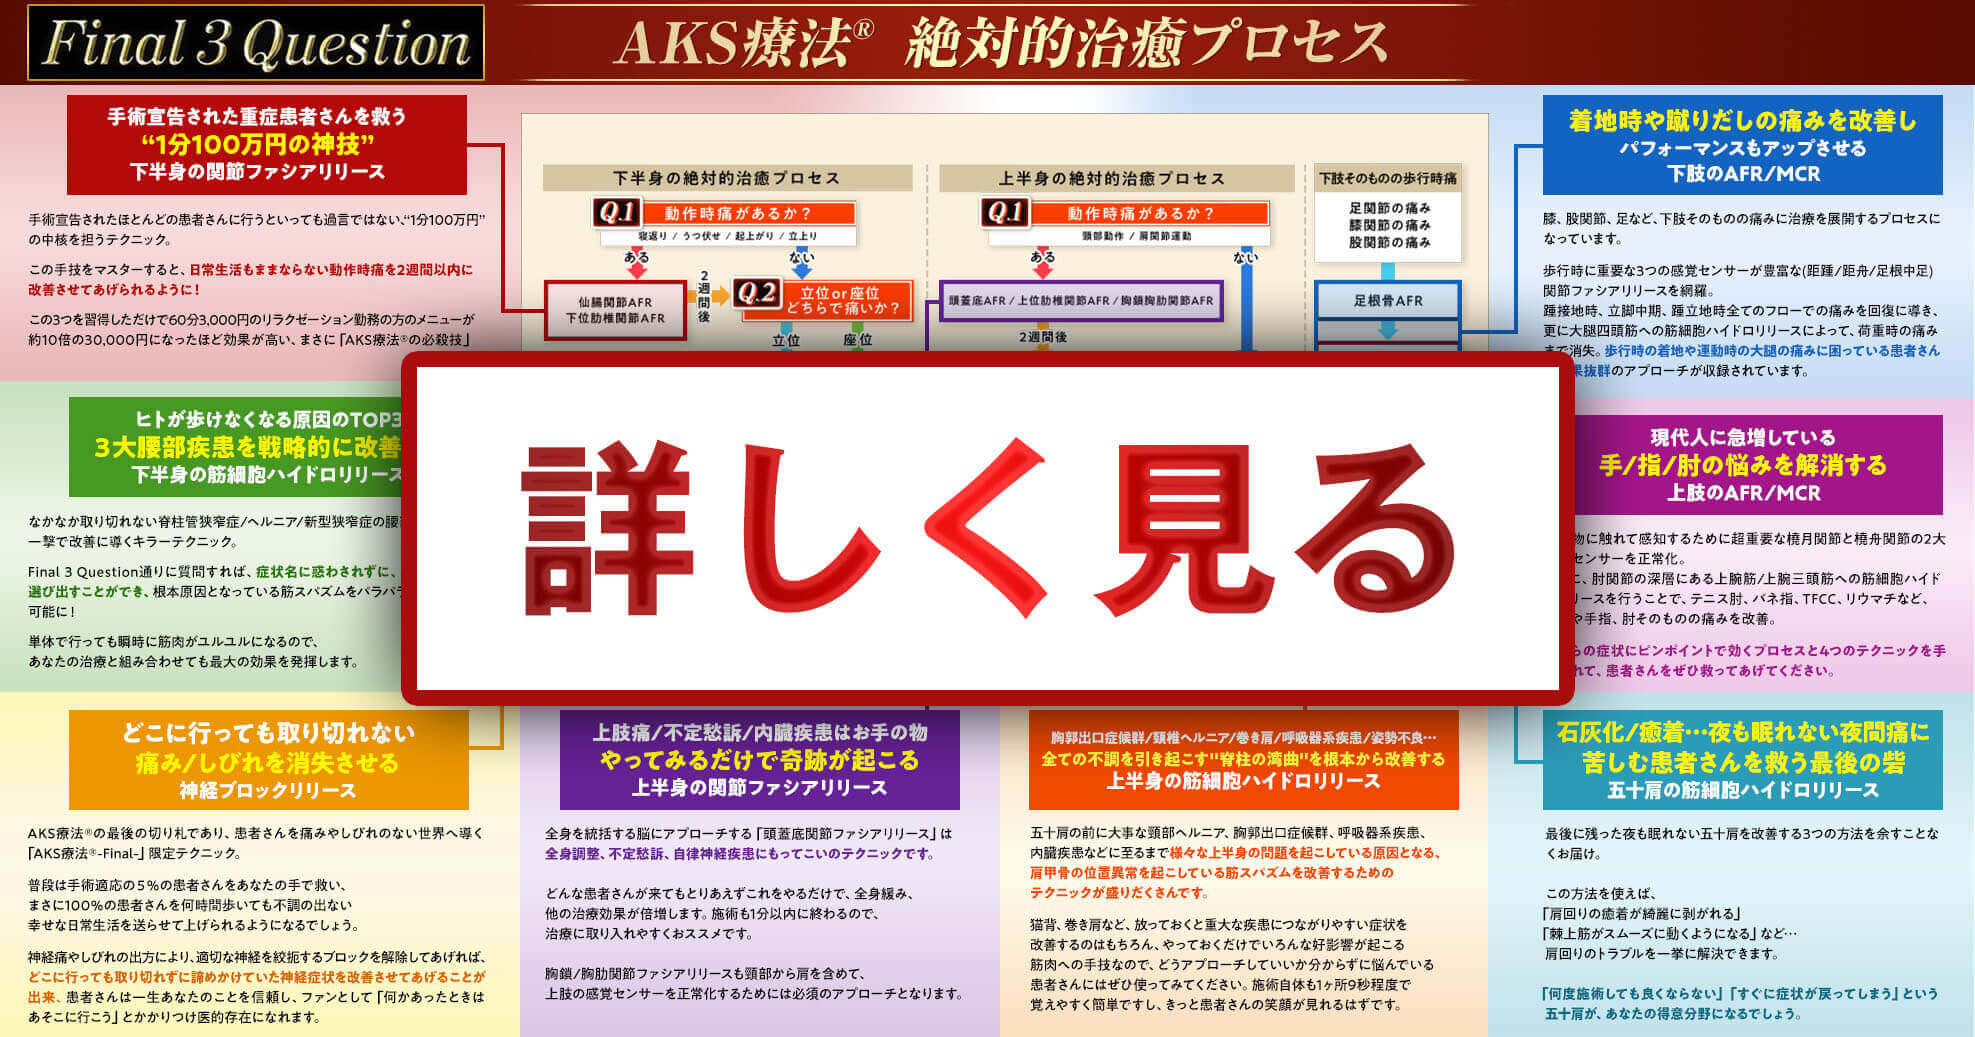

これが、AKS療法®の絶対的治癒プロセスです。この図は患者さんが来た時の問診時に使えるフローチャートになっており、あなたは上半身、下半身それぞれに対応する3つの質問「Final 3 Qestion」を患者さんに聞き、絶対的治癒プロセスに則ってチャートを進むだけで、原因が明確になり、アプローチする手技が明確になるのです。

手術宣告された重症患者さんを改善させるために

あなたがやることはたったこれだけ!

- ①フローチャートに沿って誰でも出来る3つの質問をする

⇒医師も分からない真の症状の原因が浮き彫りに! - ②チャートから導き出された手技をやるだけ

(手技自体は非常にかんたんなのでご安心ください)

かんたん2ステップでどんな重症患者さんも

改善できるようになったらいかがでしょうか?

この絶対的治癒プロセスを使えば、たとえあなたが解剖学をまったく知らない素人だとしても、患者さんの痛みの真の原因が分かるようになるので、原因が分からずに全身を揉んでみたり、治療に悩んだり不安になることがなくなるのです。

実際に私もこのプロセスを使って患者さんの問診を行ったからこそ、原因が明確になり、患者さんを回復に導くことが出来たのです。

つまり、この絶対的治癒プロセスはゴッドハンドと同じ診立てや問診、治療計画を立てるためのカンニングペーパーのようなものであり、手技の使い方をナビゲートしてくれるものです。

様々な治療法がありますが、手技のやり方を教えてくれる教材やセミナーはあっても、ここまで確固たる手技の使い方が体系化されて、プロセスチャートとしてまとまっている治療法はなかったのではないでしょうか。

この絶対的治癒プロセスがあることで、患者さんと原因を明確にしながら治療を進めていけるので、患者さんの信頼も獲得できます。

患者さんは、「病院でもここまで明確に原因を教えてくれなかった!」と、絶対的治癒プロセスを使ったあなたの問診に喜んでお金を払ってくれるようになるのです。